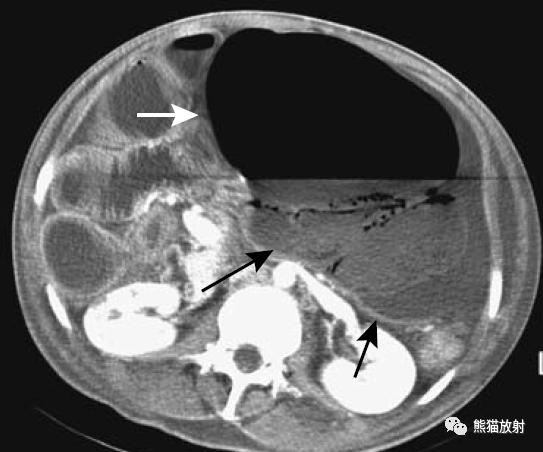

疑急性阑尾炎的患者,右半结肠癌并穿孔(箭头)。周围软组织肿块内坏死并气体影,类似阑尾脓肿表现。